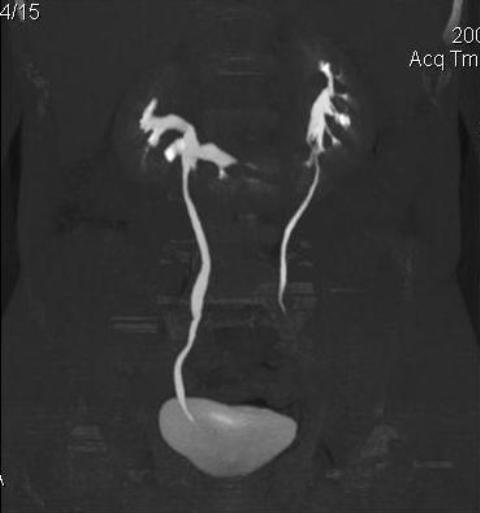

КТ Почек- подкова и уретеролитиаз

Данное наблюдение весьма демонстративно само по себе.

Ну ладно, раз никто больше не хочет, то отвечу свою версию - аномалия развития - подковообразная почка (horseshoe kidney).

Почечная колика; на последнем аксиальном скане чётко виден мелкий (2 мм) камень в устье правого мочеточника.

Для невладеющего КТ,очень четка видна аномалия на 3-4х снимках.А вот на 4-м скане в проксим.сегменте цистоида тоже есть гиперденсное точечное образование-не камень случайно?